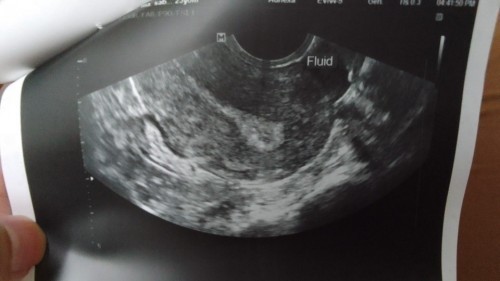

April 1 ang unang patak ng period ko, 2 days lang ang tinagal. Tas 3-18 nag spotting ako, as in patak lang. Nag consult nako, normal naman daw. Nag pa papsmear na din ako. Yung nasa left yan ang recent tvs ko, yung nasa right mga 3 months ago. Nakakakuha ako ng fainted lines na PT, minsan negative. Anyone here na nakakarelate? Gusto na kasi ng kapatid ng anak ko. ☺️#pleasehelp #advicepls